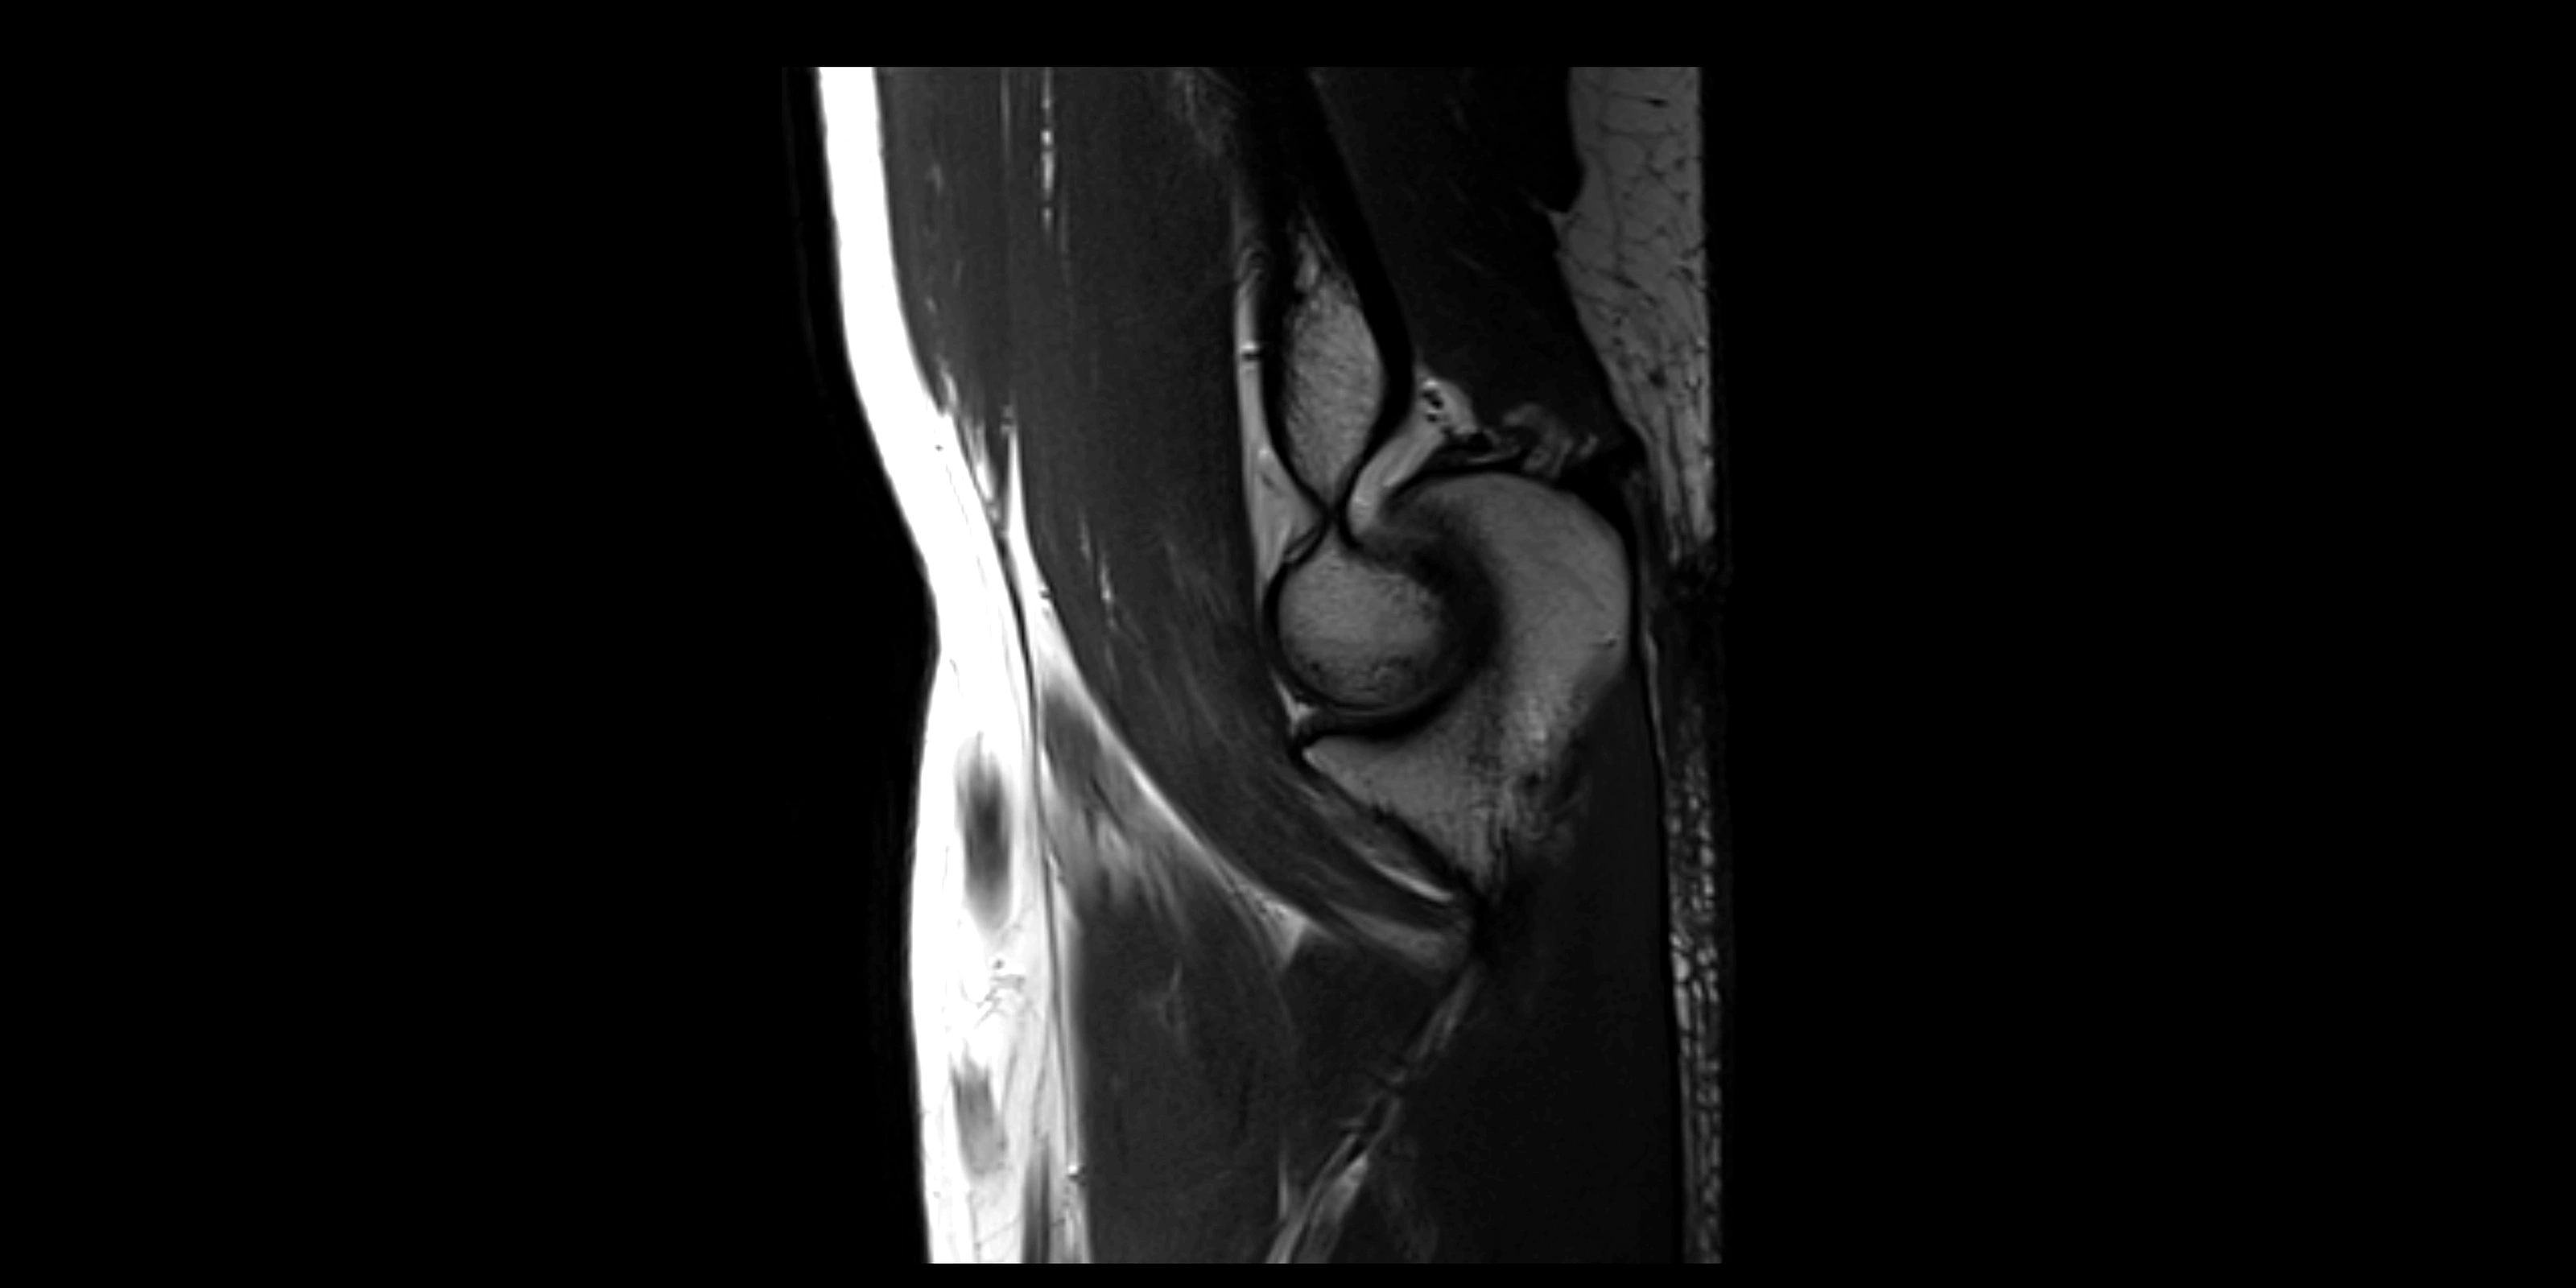

MRI images

image